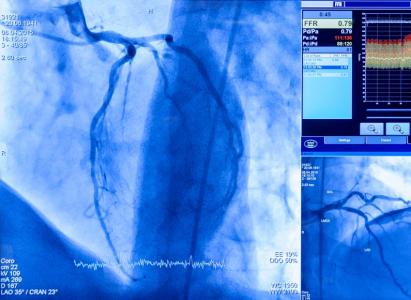

La sténose de la valve aortique (SVA) est un problème de santé important qui touche plusieurs millions de personnes dans le monde. La condition est caractérisée par des dépôts de calcium s'accumulant et rétrécissant la valve aortique, e qui contraint le cœur à travailler plus fort pour faire circuler le sang. La maladie, plus fréquente chez les personnes âgées de 65 ans et plus, évolue généralement avec des symptômes tels que des douleurs thoraciques, un essoufflement et de la fatigue.

La norme de soins actuelle est l'observation vigilante ou la surveillance active, mais elle conduit souvent à une diminution de la qualité de vie et finalement au remplacement valvulaire chirurgical.